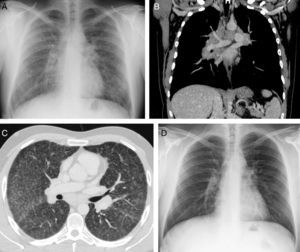

Un paciente varón de 30 años, sin antecedentes de interés, acudió a urgencias en 2007 por pérdida de visión. Se confirmó un defecto campimétrico compatible con una neuritis óptica. Ante estos hallazgos se administró un tratamiento con corticoides (1g/día durante 5 días) y se decidió realizar una resonancia magnética (RM) craneal. No se realizaron estudios radiológicos del tórax en este episodio. En la RM craneal (fig. 1) se identificaron lesiones focales en sustancia blanca, compatibles con una enfermedad desmielinizante. Dado que el paciente no cumplía todos los criterios diagnósticos de esclerosis múltiple (EM) y que no presentaba nuevos episodios de focalidad neurológica durante el seguimiento, se decidió no instaurar un tratamiento específico y realizar un seguimiento ambulatorio.

RM de cráneo. Imagen sagital potenciada en T2 (A) en la que se observa una lesión focal hiperintensa en el esplenio del cuerpo calloso (flecha blanca). Imagen axial FLAIR (B) en la que se visualiza una lesión focal hiperintensa en la sustancia blanca periventricular (flecha blanca). Ambas lesiones son inespecíficas desde el punto de vista radiológico, pero en un contexto clínico adecuado compatibles con una enfermedad desmielinizante.